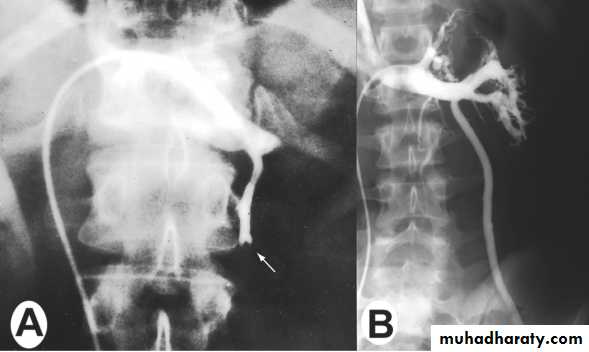

• Venography

• The best tool to diagnose varicocele & to treat it by embolization (via femoral or internal iliac veins).• Ultrasonography (US)

1.embolization.